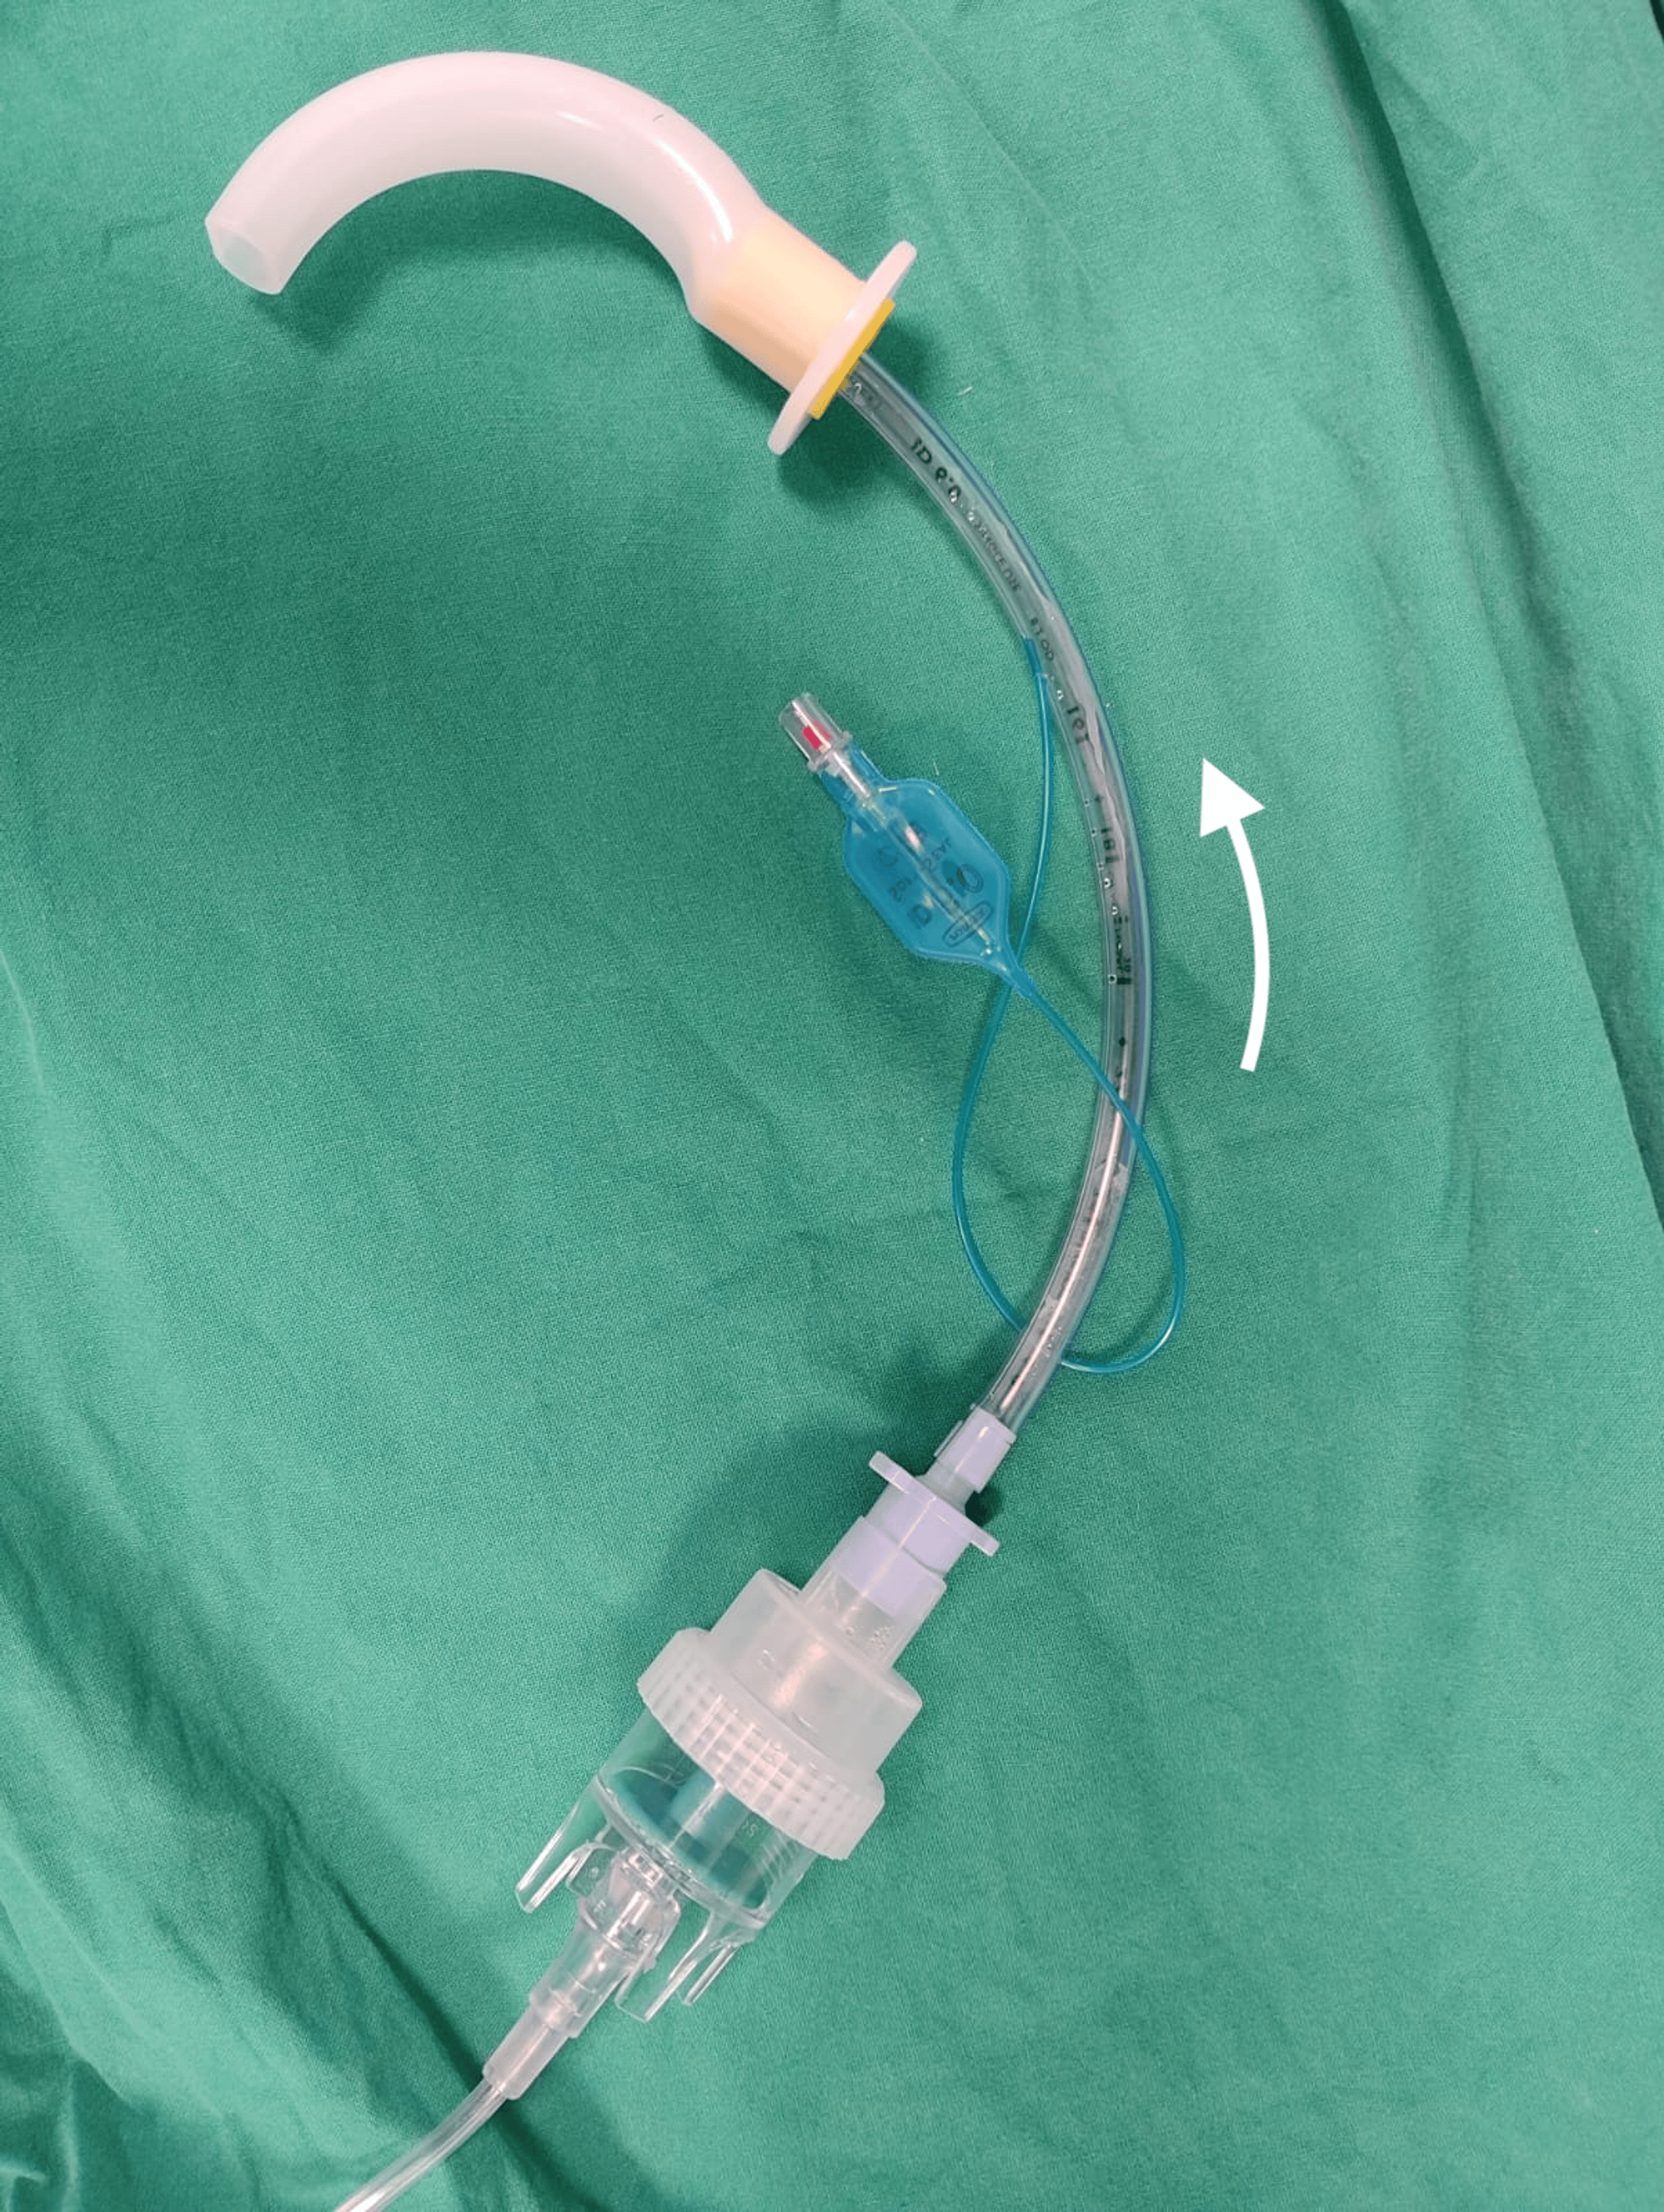

The first assembly is demonstrated in Figure 1.

This is an assembly of connected equipment in the following order: oxygen tubing (connected to an auxiliary oxygen outlet running at 8 L/min), nebulizer chamber (containing 4 ml of 2% lignocaine), endotracheal tube (ETT), Guedel airway. If possible, we suggest using the ETT of choice for subsequent intubation to reduce wastage; otherwise, a size 6 ETT fits well with this assembly. The Guedel airway is then inserted by the patient into their own mouth and advanced as tolerated, while being gently held in place by the anesthetic team during nebulization (Figure 2). Sizing of the Guedel airway is in accordance with standard sizing, from the corner of the patient’s mouth to the angle of the mandible [7].

Before this is done, the posterior tongue to the oropharynx needs to be topicalized either with LA spray or directly via nebulization using this equipment assembly. The former was used in Case 1 and the latter in Case 4. This technique aims to direct the LA to specifically target the laryngeal inlet. It is necessary to interpose an ETT between the oral airway and the nebulizer to keep the nebulizer chamber upright. The length of the ETT is retained for two reasons: firstly, to provide the curvature required for the nebulizer chamber to remain upright, if the ETT were shorter, the chamber may be slanted, resulting in inefficient nebulization. Secondly, we try to use the same ETT for subsequent intubation where possible, saving an additional piece of equipment.